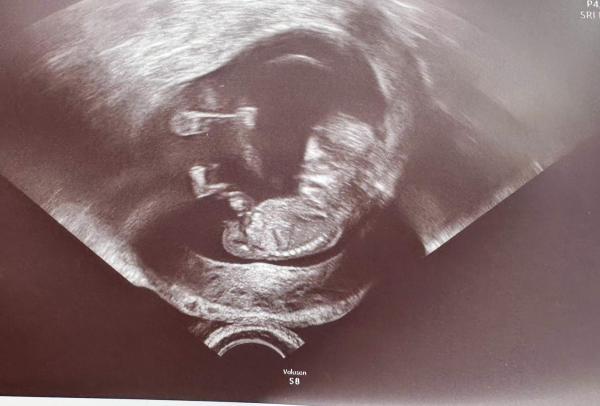

Hei, hier war vor kurzem ein Beitrag zum Thema Nub. Ich kenn mich damit gar nicht aus, weiß nicht mal ob ein Nub zu sehen ist auf dem Bild. Was meint ihr? Bin gespannt auf eure Einschätzungen

Hey, ich kenne die Nub Theorie, aber dazu scheiden sich ja bekanntlich die Geister. Denke der Nub wäre wenn auch weiter unten, was man im Netz so sieht. Auf jeden Fall total süßes Foto Was mich auch fasziniert ist einfach, dass Mädels und Jungs bis ca. 20 Woche gleich aussehen. Bei Mädels wächst es dann rein und bei Jungs eben nicht. Natur ist einfach Wahnsinn!

Hi Sandra! Ich habe mich ein bisschen mit der Theorie beschäftigt und - falls diese "Zacke" bei dir der NUB ist, würde ich - aber ich bin natürlich Laie - auf einen Jungen tippen. Viele Grüße! :-)